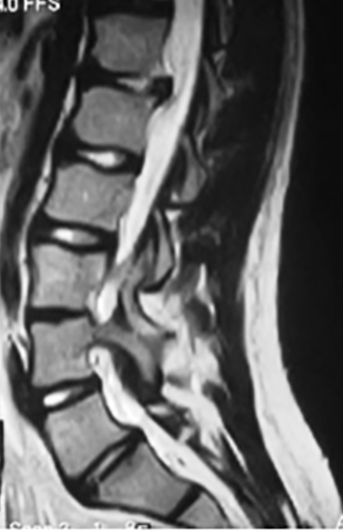

Es menos frecuente que en la población adulta, un 2% de la población pediátrica sufrirá de un disco herniado (21). Usualmente va a estar acompañado de un historial familiar positiva o de traumatismo. El paciente refiere dolor que se irradia hasta las piernas y que aumenta con actividades tan simples como estornudar, estar sentado o parado. El examen físico mostrará un paciente inclinado hacia el frente, con limitación de movimiento de la columna vertebral y dolor al levantar las piernas. El examen neurológico reflejará la disminución de algún reflejo, debilidad o adormecimiento aunque es menos frecuente este hallazgo en los niños que en los adultos (22). La radiografía puede mostrar una escoliosis reactiva al dolor o una disminución del espacio intervertebral, pero el mejor estudio es la RM (Figura 1). El tratamiento inicial será modificar las actividades, procurar descanso y medicación analgésica, relajantes musculares, infiltraciones epidurales y terapia física. Si no hay una respuesta adecuada al manejo conservador o hay alteración neurológica, estará indicada la remoción quirúrgica del disco herniado (22).